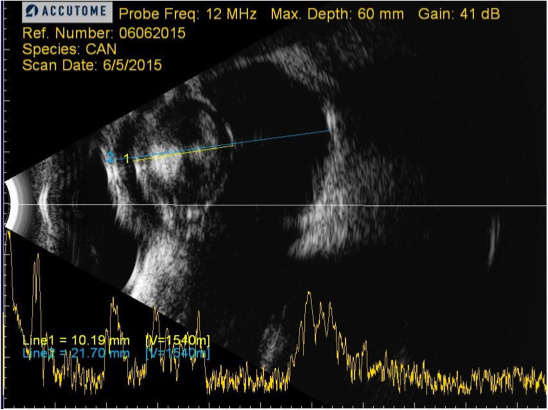

Se puede apreciar la diferencia significativa de un ojo microftálmico como es el de Tommy y uno de otro paciente, con un tamaño ocular normal pero también con hiperecogenicidad a nivel del cristalino debido a una catarata:

Los ojos microftálmicos tienen una longitud axial menor, por lo que no tienen las mismas dioptrías, un factor importante a la hora de querer que nuestros pacientes sean lo más próximos a un emétrope tras la cirugía de cataratas.

Debido a la microftalmia de Tommy, las lentes intraoculares (LIO) debían ser de 30 dioptrías (D).